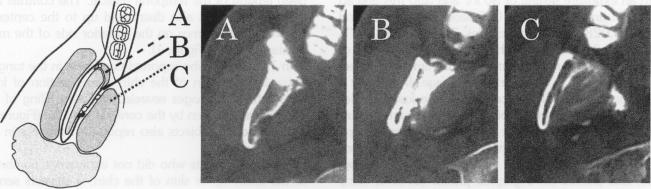

We studied the spread of local anesthetic solution in the inferior alveolar nerve block by the injection of local anesthetic solution into the pterygomandibular space anterior to the mandibular foramen (anterior technique). Seventeen volunteers were injected with 1.8 mL of a mixture containing lidocaine and contrast medium utilizing the anterior technique. The course of spread was traced by fluoroscopy in the sagittal plane, and the distribution area was evaluated by lateral cephalograms and horizontal computed tomography. The results indicate that the contrast medium mixture spreads rapidly in the pterygomandibular space to the inferior alveolar nerve in the subjects who exhibited inferior alveolar nerve block effect. We concluded that the anesthetic effect due to the anterior technique was produced by the rapid distribution of anesthetic solution in the pterygomandibular space toward the mandibular foramen, and individual differences in the time of onset of analgesia may be due to differences in the histologic perineural tissues.

我们通过在下颌孔前方的翼下颌间隙注射局部麻醉溶液(前入路技术),研究了下牙槽神经阻滞中局部麻醉溶液的扩散情况。17名志愿者采用前入路技术注射了1.8 mL含利多卡因和造影剂的混合溶液。通过矢状面荧光透视追踪扩散过程,并通过侧位头影测量片和水平计算机断层扫描评估分布区域。结果表明,在表现出下牙槽神经阻滞效果的受试者中,造影剂混合溶液在翼下颌间隙迅速扩散至下牙槽神经。我们得出结论,前入路技术产生的麻醉效果是由于麻醉溶液在翼下颌间隙中迅速向下颌孔分布,而镇痛起效时间的个体差异可能归因于神经周围组织学的差异。